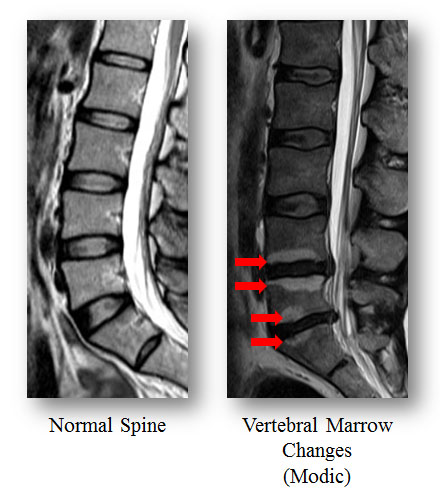

Low back pain (LBP) is a leading cause of ill-health and sick leave in the working population of Hong Kong. Many people suffering from LBP have tried many different treatments but the outcomes are unsatisfactory. The Department of Orthopaedics and Traumatology, Li Ka Shing Faculty of Medicine, The University of Hong Kong (HKU) has carried out the largest population-based study addressing spine degeneration on magnetic resonance imaging (MRI) and LBP since 2001 and found specific patterns of vertebral marrow changes, known as “Modic changes”, that are highly associated with intervertebral disc degeneration. This groundbreaking study identifying the source of LBP through checking Modic changes on MRI has been published in the latest issue of Medicine (http://journals.lww.com/md-journal/Fulltext/2016/05310/Refined_Phenotyping_of_Modic_Changes__Imaging.5.aspx).

A large-scale population based study consisting of 1,142 individuals of Southern Chinese origin in Hong Kong was undertaken. All of these individuals had undergone MRI of their lumbar spine and clinical assessment. The images were assessed for a variety of spine degeneration, such as Modic changes, and mapped to different patterns and sub-types of spine changes (e.g. disc degeneration, disc herniation). These findings were then assessed to determine their role in different stages of LBP and disability.

63% of the subjects are female and the mean age of the subjects is 53 years old. Of these, 282 (24.7%) had Modic changes, with 7.1% belong to type I (indicating marrow edema in endplate disruption and vascular granulation tissue) and the other 17.6% belong to type II (indicating fatty degeneration of the vertebral marrow). Modic changes subjects were older, had more frequent disc displacements and greater degree of disc degeneration than non-Modic changes subjects. After adjusted for confining factors, Modic changes were associated with prolonged severe LBP. Type I Modic changes tended to associate with pain more strongly than type II Modic changes, while type II Modic changes were more associated with disability. The strength of associations with pain and disability increased with the extent and number of Modic changes involving in different vertebral levels.

This large-scale study represents one of the first to date to extensively assess the clinical relevance of distinct Modic changes. The results showed that specific Modic changes types and patterns were associated with prolonged severe LBP and disability. These findings strengthen the clinical importance of Modic changes as key “imaging biomarkers” among LBP patients. This study raises awareness on the need to assess specific Modic changes types regarding their morphology and extent of involvement of the spine, which may contribute to the understanding of LBP development and severity. The study assists doctors in performing clinical assessment more accurately.